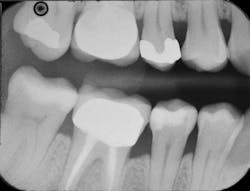

The final radiograph of No. 29's distal and occlusal surfaces shows no evidence of the adhesive layer, thanks to the low film thickness of Prime&Bond Elect, which helps to ensure excellent cavity adaptation and prevent black lines on radiographs that could be misdiagnosed as voids or recurrent caries (figure 5).

Figure 5: The final radiograph of the completed restoration on No. 29